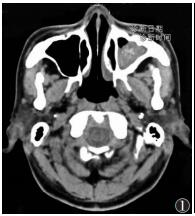

2.2 CT表现 2.2.1 窦腔改变32例病变窦腔密度不均,内见单发或多发斑片状、结节状及团块状略高密度影,CT值48~80 HU,软组织密度影完全充填窦腔25例,部分充填窦腔7例,病灶周围有紧贴窦腔内壁的低密度影环绕;病变内见钙化13例(图 1),其中8例呈沙砾状钙化,5例呈条状钙化,CT值80~180 HU,钙化灶多位于上颌窦内上区窦口附近。

| 图 1 男,65岁,真菌性上颌窦炎。左侧上颌窦软组织影部分充填,内有多发斑点状钙化,窦壁增厚 |